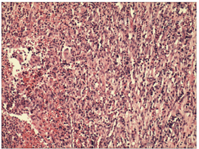

完善术前准备,予以在全麻下行剖腹探查术,术中见:腹腔内无积液,肝、胃、十二指肠未见异常,右上腹轻度粘连,中腹部距离屈氏韧带约40 cm处可见一大小约9 cm×7 cm×5 cm包块,与腹壁、大网膜、回肠及横结肠粘连严重,锐钝性相结合分离包块与周围的粘连后发现肿块下缘与空肠形成内瘘,瘘口旁坏死组织内可见一长约1 cm质硬条状物,形似鱼骨刺,考虑质硬条状物刺破肠管形成炎性包块,因瘘口周围肠管炎症水肿较重,遂术中即行包块切除+病变段肠管切除+空肠侧侧吻合术,术后恢复良好,治愈出院。病理检查:包块内增生性纤维胶原组织伴多量浆细胞、嗜酸性粒细胞浸润,部分区出血、坏死,大量中性粒细胞浸润,考虑炎症性病变(见封四,图2)。